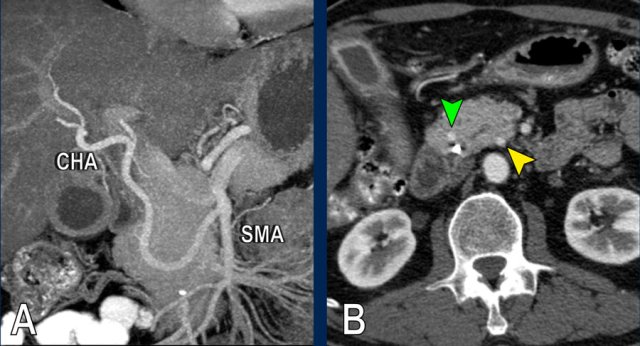

The use of multiplanar reformations improves overall CT performance as seen in this case.

A coronal reformat shows a small tumor in the pancreatic head (arrowheads) with obstruction of the common bile duct.

There seems to be just limited contact with the portal vein (arrow).

Continue with the next images.

A multiplanar reformat perpendicular to the portal vein shows that there is more extensive contact with the portal vein, 90 – 180 degrees (arrow).

Without contour irregularity this is classified as borderline resectable according to the DPCG criteria but resectable according to the NCCN criteria.

Resection without venous reconstruction proved to be R1, meaning presence of microscopic tumor invasion of the resection margin.